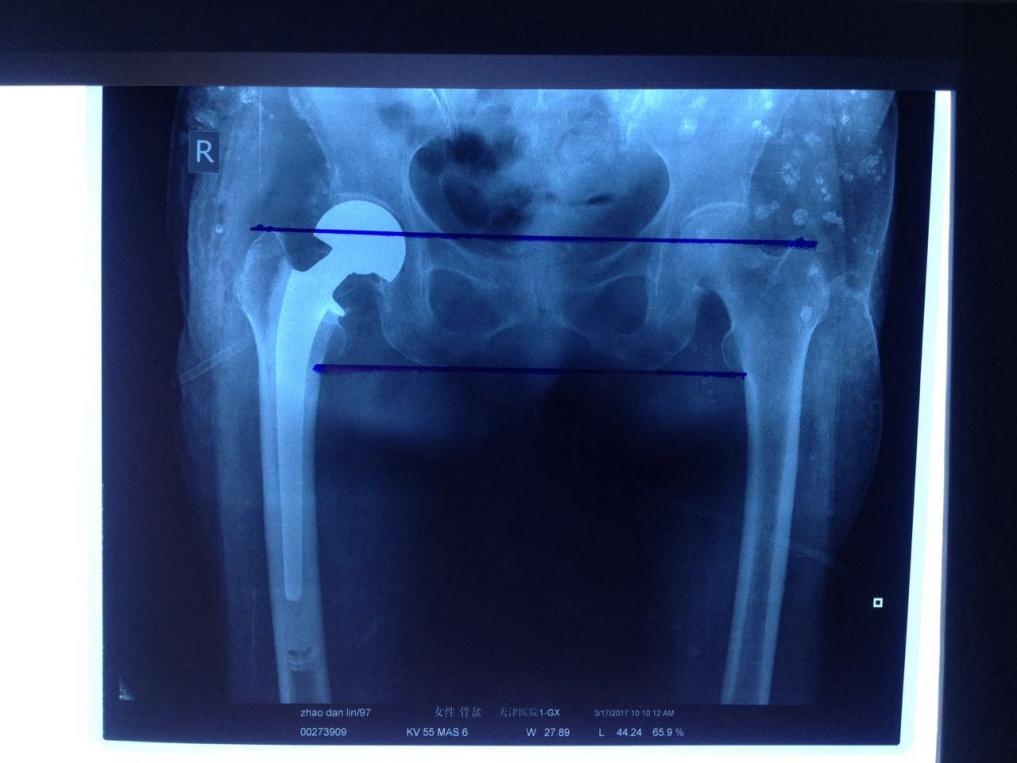

97岁的赵奶奶在家中扫地时,因站立不稳,跌倒在地,髋部顿时疼痛难忍,活动受限,无法站立,家人立即将老人送至天津医院急诊科就医,X光片检查显示为右股骨颈骨折,移位明显,需尽快手术治疗。在同一天接诊的患者中,93岁的孙奶奶也是因在家中不慎跌倒导致了右股骨颈骨折收住入院。

两名老人入院后,进入了老年髋部骨质疏松骨折诊疗流程,X光片检查显示为右股骨颈骨折,移位明显,需尽快手术治疗。在急诊迅速完成检验、放射等相关检查,进入病房后主管医师立即完善临床检查及相应的抗凝、补液等对症治疗。创伤骨科髋关节一病区王裕民主任迅速组织科室讨论,制定了周密的手术计划。

经过充分准备,在两位老人入院后的72小时内,同一天安排了手术。在麻醉科术中支持下,王裕民主任迅速地为两位老人实施半髋关节置换手术,手术时间平均35分钟左右,出血都低于100ml,术后安返病房。术后三天老人两位老人术后恢复良好,复查各项指标正常,在王裕民主任的指导下,两位老人已能使用助行器下地负重行走。